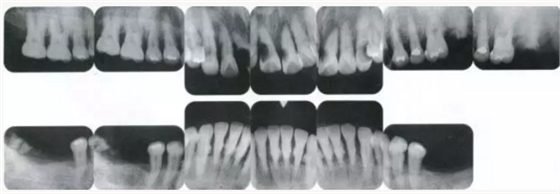

▲圖19-1

40歲,女性。來院主訴為牙齦出血,牙體晃動?;颊卟晃鼰?,因此沒有全身性問題。有明顯的牙周炎,發(fā)生了牙體移動,前牙區(qū)前突。下頜右側磨牙缺失,醫(yī)生認為有必要進行包括牙周修復、正畸治療、種植治療等在內的綜合性治療。

▲圖19-2,3

上下頜咬合面照。

▲圖19-4

X光片。牙槽骨明顯缺失。